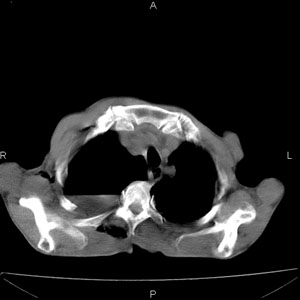

患者男,77岁,于3日前从树上摔下,头部查ct示蛛血,硬膜下出血,上腹部ct未见明显异常,右侧胸腔积液,左侧如常。肺部拍片示右侧肋骨多发骨折住院后今日来查肺部ct,我看到的是1。右侧胸腔血气胸并右肺上叶,中叶压缩性肺不张,2。右肺下叶肺挫伤并多发肋骨骨折,肌内及皮下积气3。左侧少量胸腔积液,我想请教的是3天前左侧胸腔里没有积液今天怎么出现了呢,是什么原因呢?请讨论。

右侧多发肋骨骨折,同侧液气胸